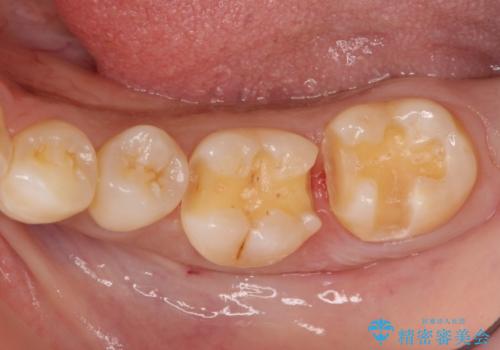

左下の奥歯2本にプラスチックの詰め物がされており、一見虫歯には見えない状態でした。

レントゲンを撮影したところ、奥歯の歯の間が虫歯が発見できました。

古い詰め物を取り、虫歯を除去して、合わせた形でセラミックインレーで治療しました。